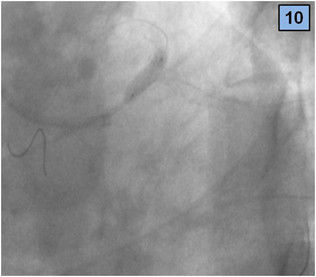

4. A 3.5 x 18 mm zotarolimus DES was placed from medium LM to proximal LAD artery through the LM – CX stent (Figure 10), and a new guidewire was recrossed to the CX (Figure 11).

Figure 10 DES implantation (from medium LM to proximal LAD).